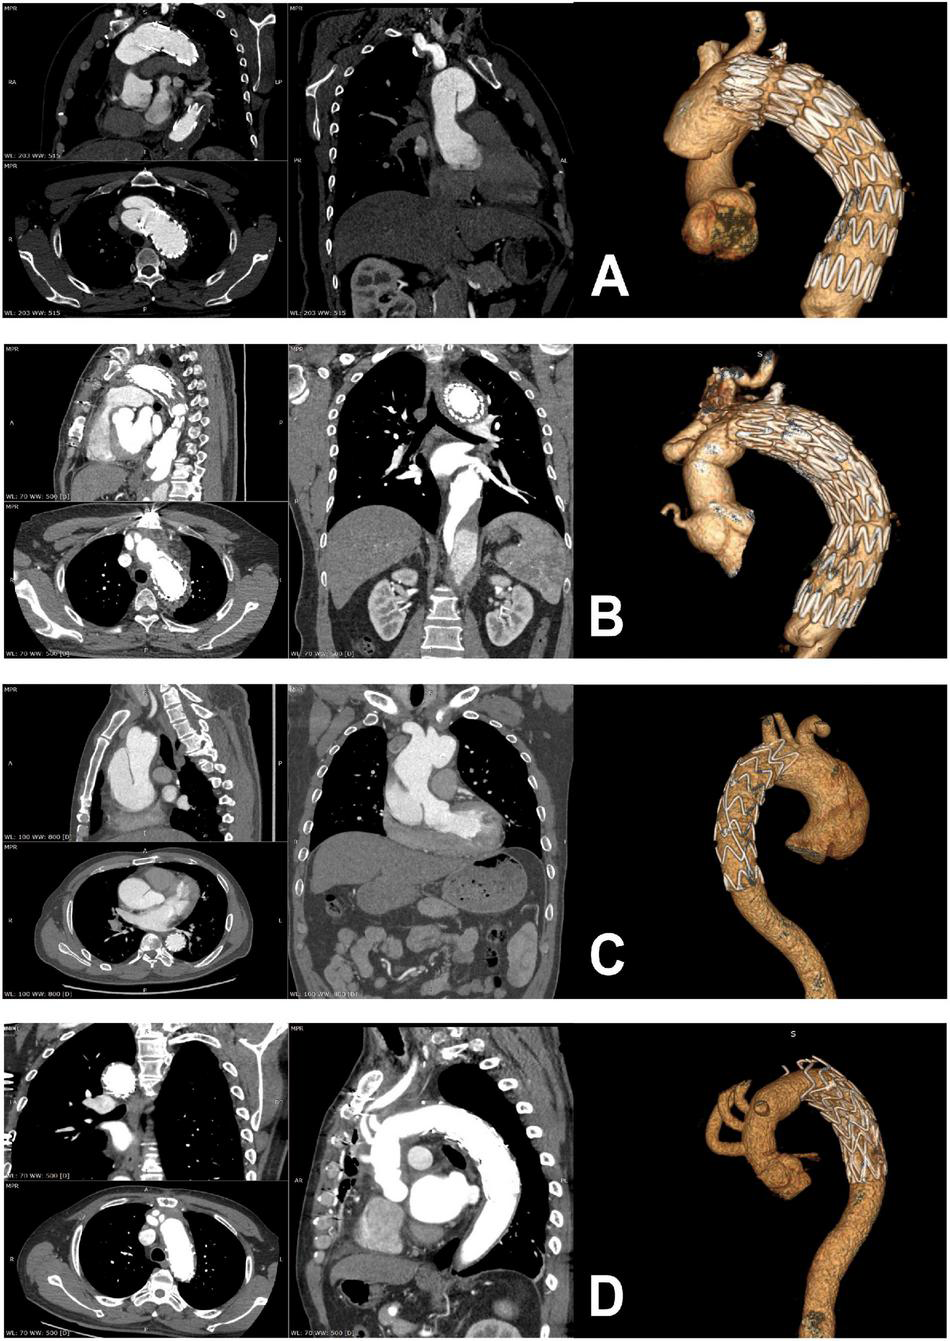

FIGURE 1

Preoperative and postoperative computed tomographic scans of patients with retrograde type A dissection (A,B) and antegrade type A dissection (C,D).